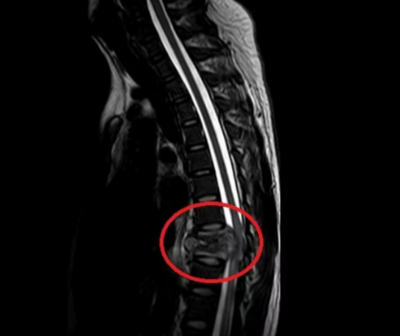

胸椎7-8椎体结核伴脓肿形成压迫脊髓

入院后,脊柱外科二区主任曾浩为他进行了详细问诊与系统查体,诊断袁江为胸椎7-8椎体结核合并不全瘫痪。经过科室讨论,并与患者和家属进行了详细的沟通,曾主任决定为他进行单纯后路胸椎结核病灶清除+椎管减压+椎间钛网植骨融合+椎弓根螺钉内固定术。手术过程非常顺利,术后袁江继续接受抗结核、护肝、康复等对症支持治疗。现在袁江背痛已基本消失,双下肢感觉活动恢复良好,在支具保护下可下地活动。